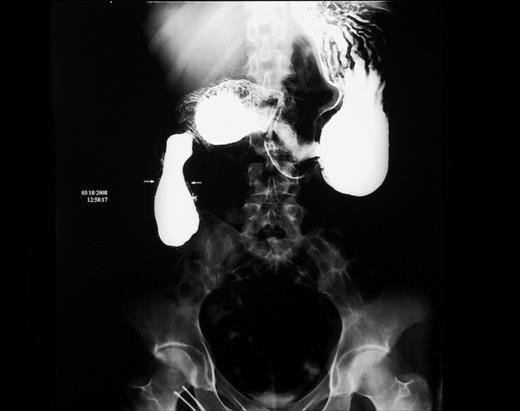

Upper gastrointestinal series showed the presence of an intraluminal duodenal diverticulum of about 8 cm in length and a partially occluded duodenal lumen (figure 1).

Upper gastrointestinal series. Intraluminal duodenal diverticulum, pear-shaped sac, occluding duodenal lumen (arrows).